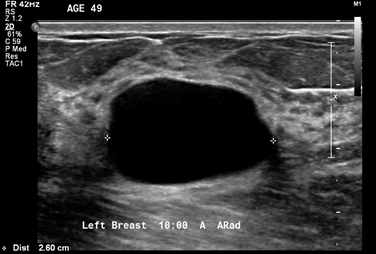

- The patient has a BIRADS 2 simple cyst

- To be regarded as a simple cyst, a breast nodule must meet three criteria:

- The margins must be circumscribed:

- i.e., a margin “that is well defined or sharp, with an abrupt transition between the lesion and surrounding tissue”

- It must be anechoic:

- i.e., “without internal echoes”

- It must show posterior acoustical enhancement:

- i.e., “a column that is more echogenic deep to the mass”

- Simple cysts:

- Are almost never associated with cancer in the absence of other abnormalities seen on mammogram or ultrasound

- In the image shown, a hyperechoic band can be seen within or just above the anterior wall of the cyst, especially on the left side of the image:

- The acoustic mismatches between this band and the less echogenic tissue superficial to it and the anechoic fluid deep to it, cause echoes that reverberate, creating the artifact in the near field of the cyst